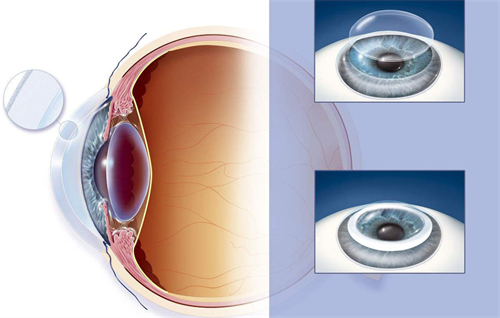

孙医生在玻璃体视网膜手术方面具有独特技术优势,采用国内外靠前的小创口玻璃体切割技术治疗复杂性视网膜脱离,手术成功几率达90%以上。

手术过程解析

典型玻璃体手术包含三个关键阶段:

术前准备:超全评估全身状况,定制个性化玻璃体替代方案

精细操作:在显微镜下完成视网膜前膜剥离、激光光凝等步骤

术后管理:采用特殊体位护理,配合***药物治疗

孙医生团队特别重视围手术期视觉质量评估,运用微脉冲激光等新技术更大限度保护视功能。